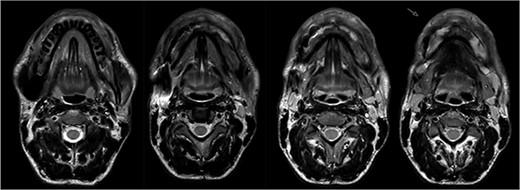

In 2020, a 99 m Technetium scintigraphy was performed to rule out disseminated osteomyelitis. The scintigraphy showed no other foci of enhancement but the mandible with increased inflammatory activity in the anterior portion of the jaw (Fig. 1). Magnetic resonance imaging (MRI) was performed to analyze the localization and extent of the disease. In Fig. 2, a high inflammatory activity, resembled by a strong local enhancement in the T2 weighting, was seen, reaching from the right condyle to the left. Cone beam computed tomography (CBCT) confirmed a widespread patchy radiolucency extending to both left and right mandibular condyles (Fig. 3). Hard tissue biopsies were taken to rule out malignancy due to the disease’s extensive destruction and chronic course. Blood assays were also requested.

Magnetic resonance imaging (MRI) before bisphosphonate therapy (axial sections). T2 weighting of the MRI shows the high inflammatory activity especially in the anterior portion of the mandible (arrow).